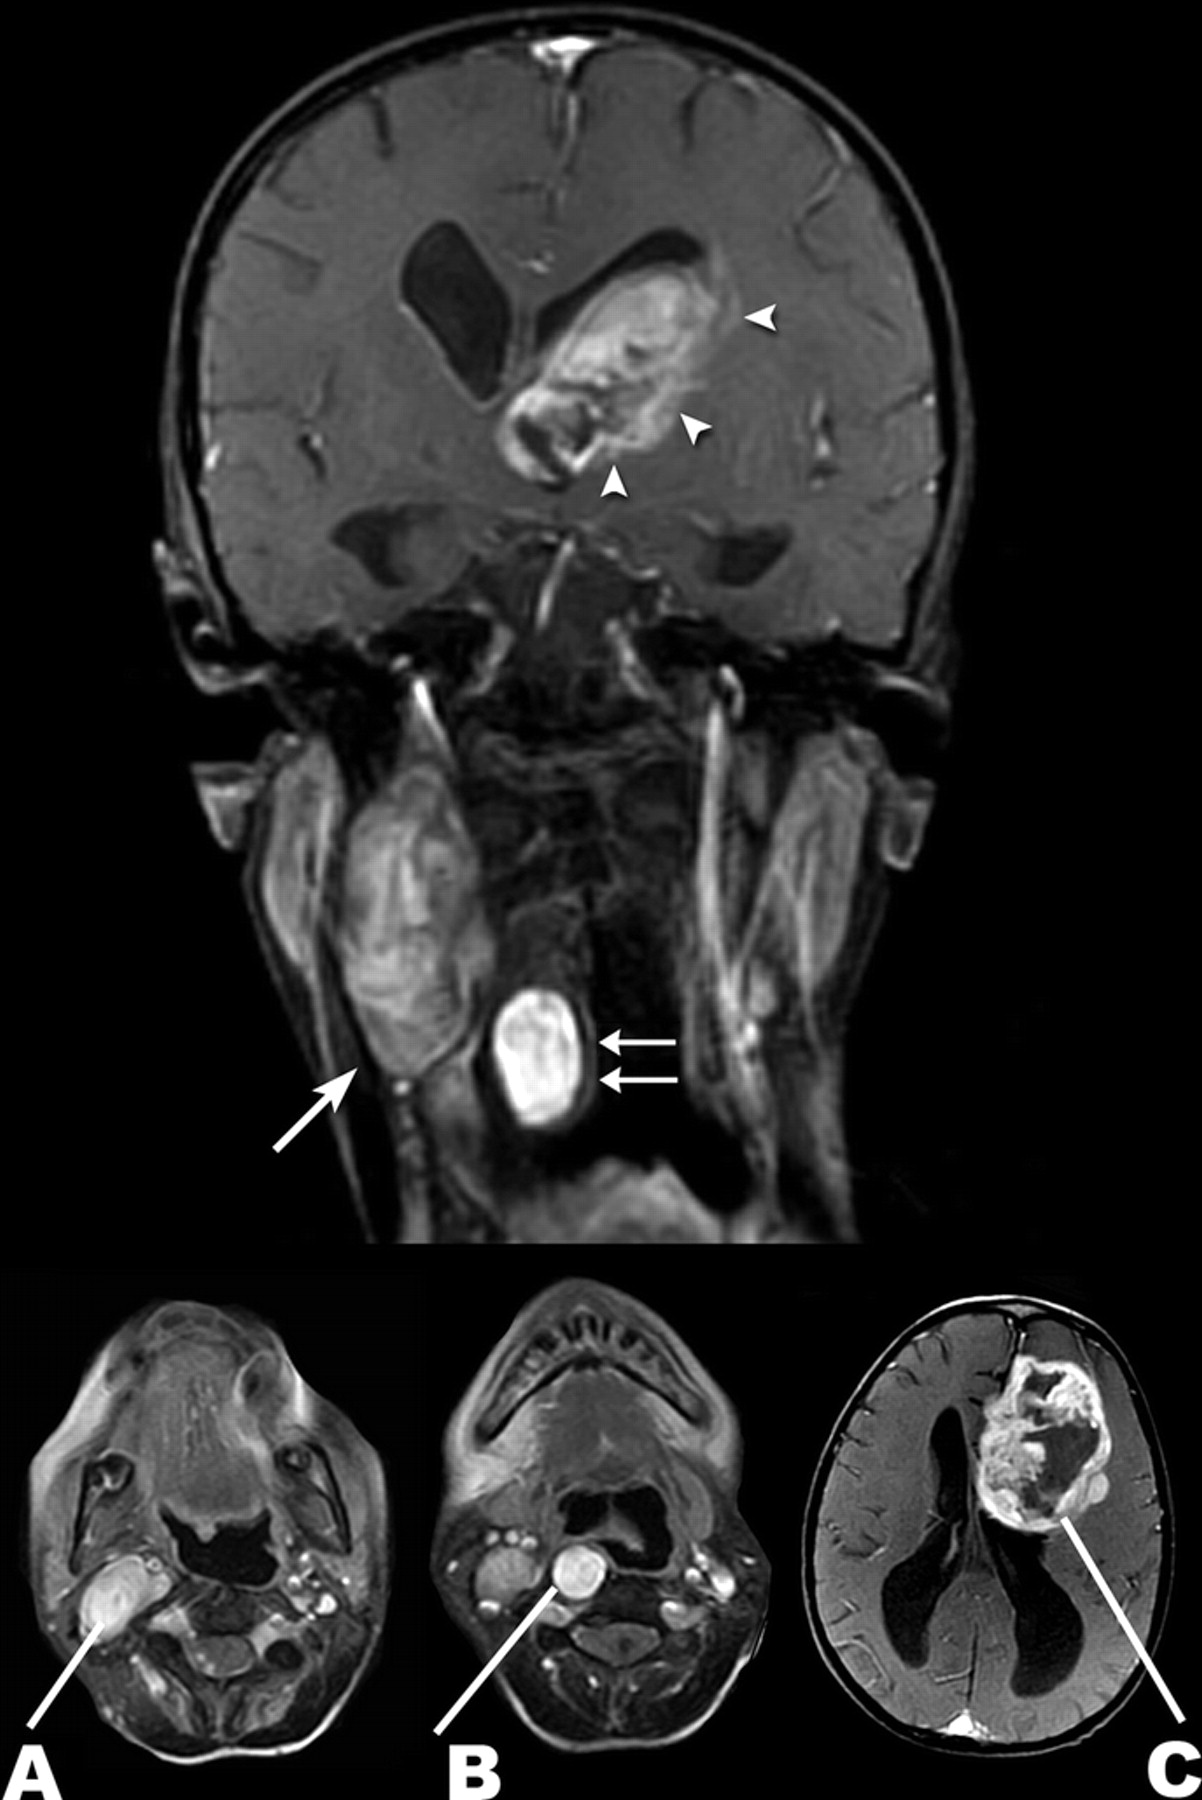

良性和恶性病理神经纤维瘤病1型

梅勒妮•沃克,帕特里克•Gabikian